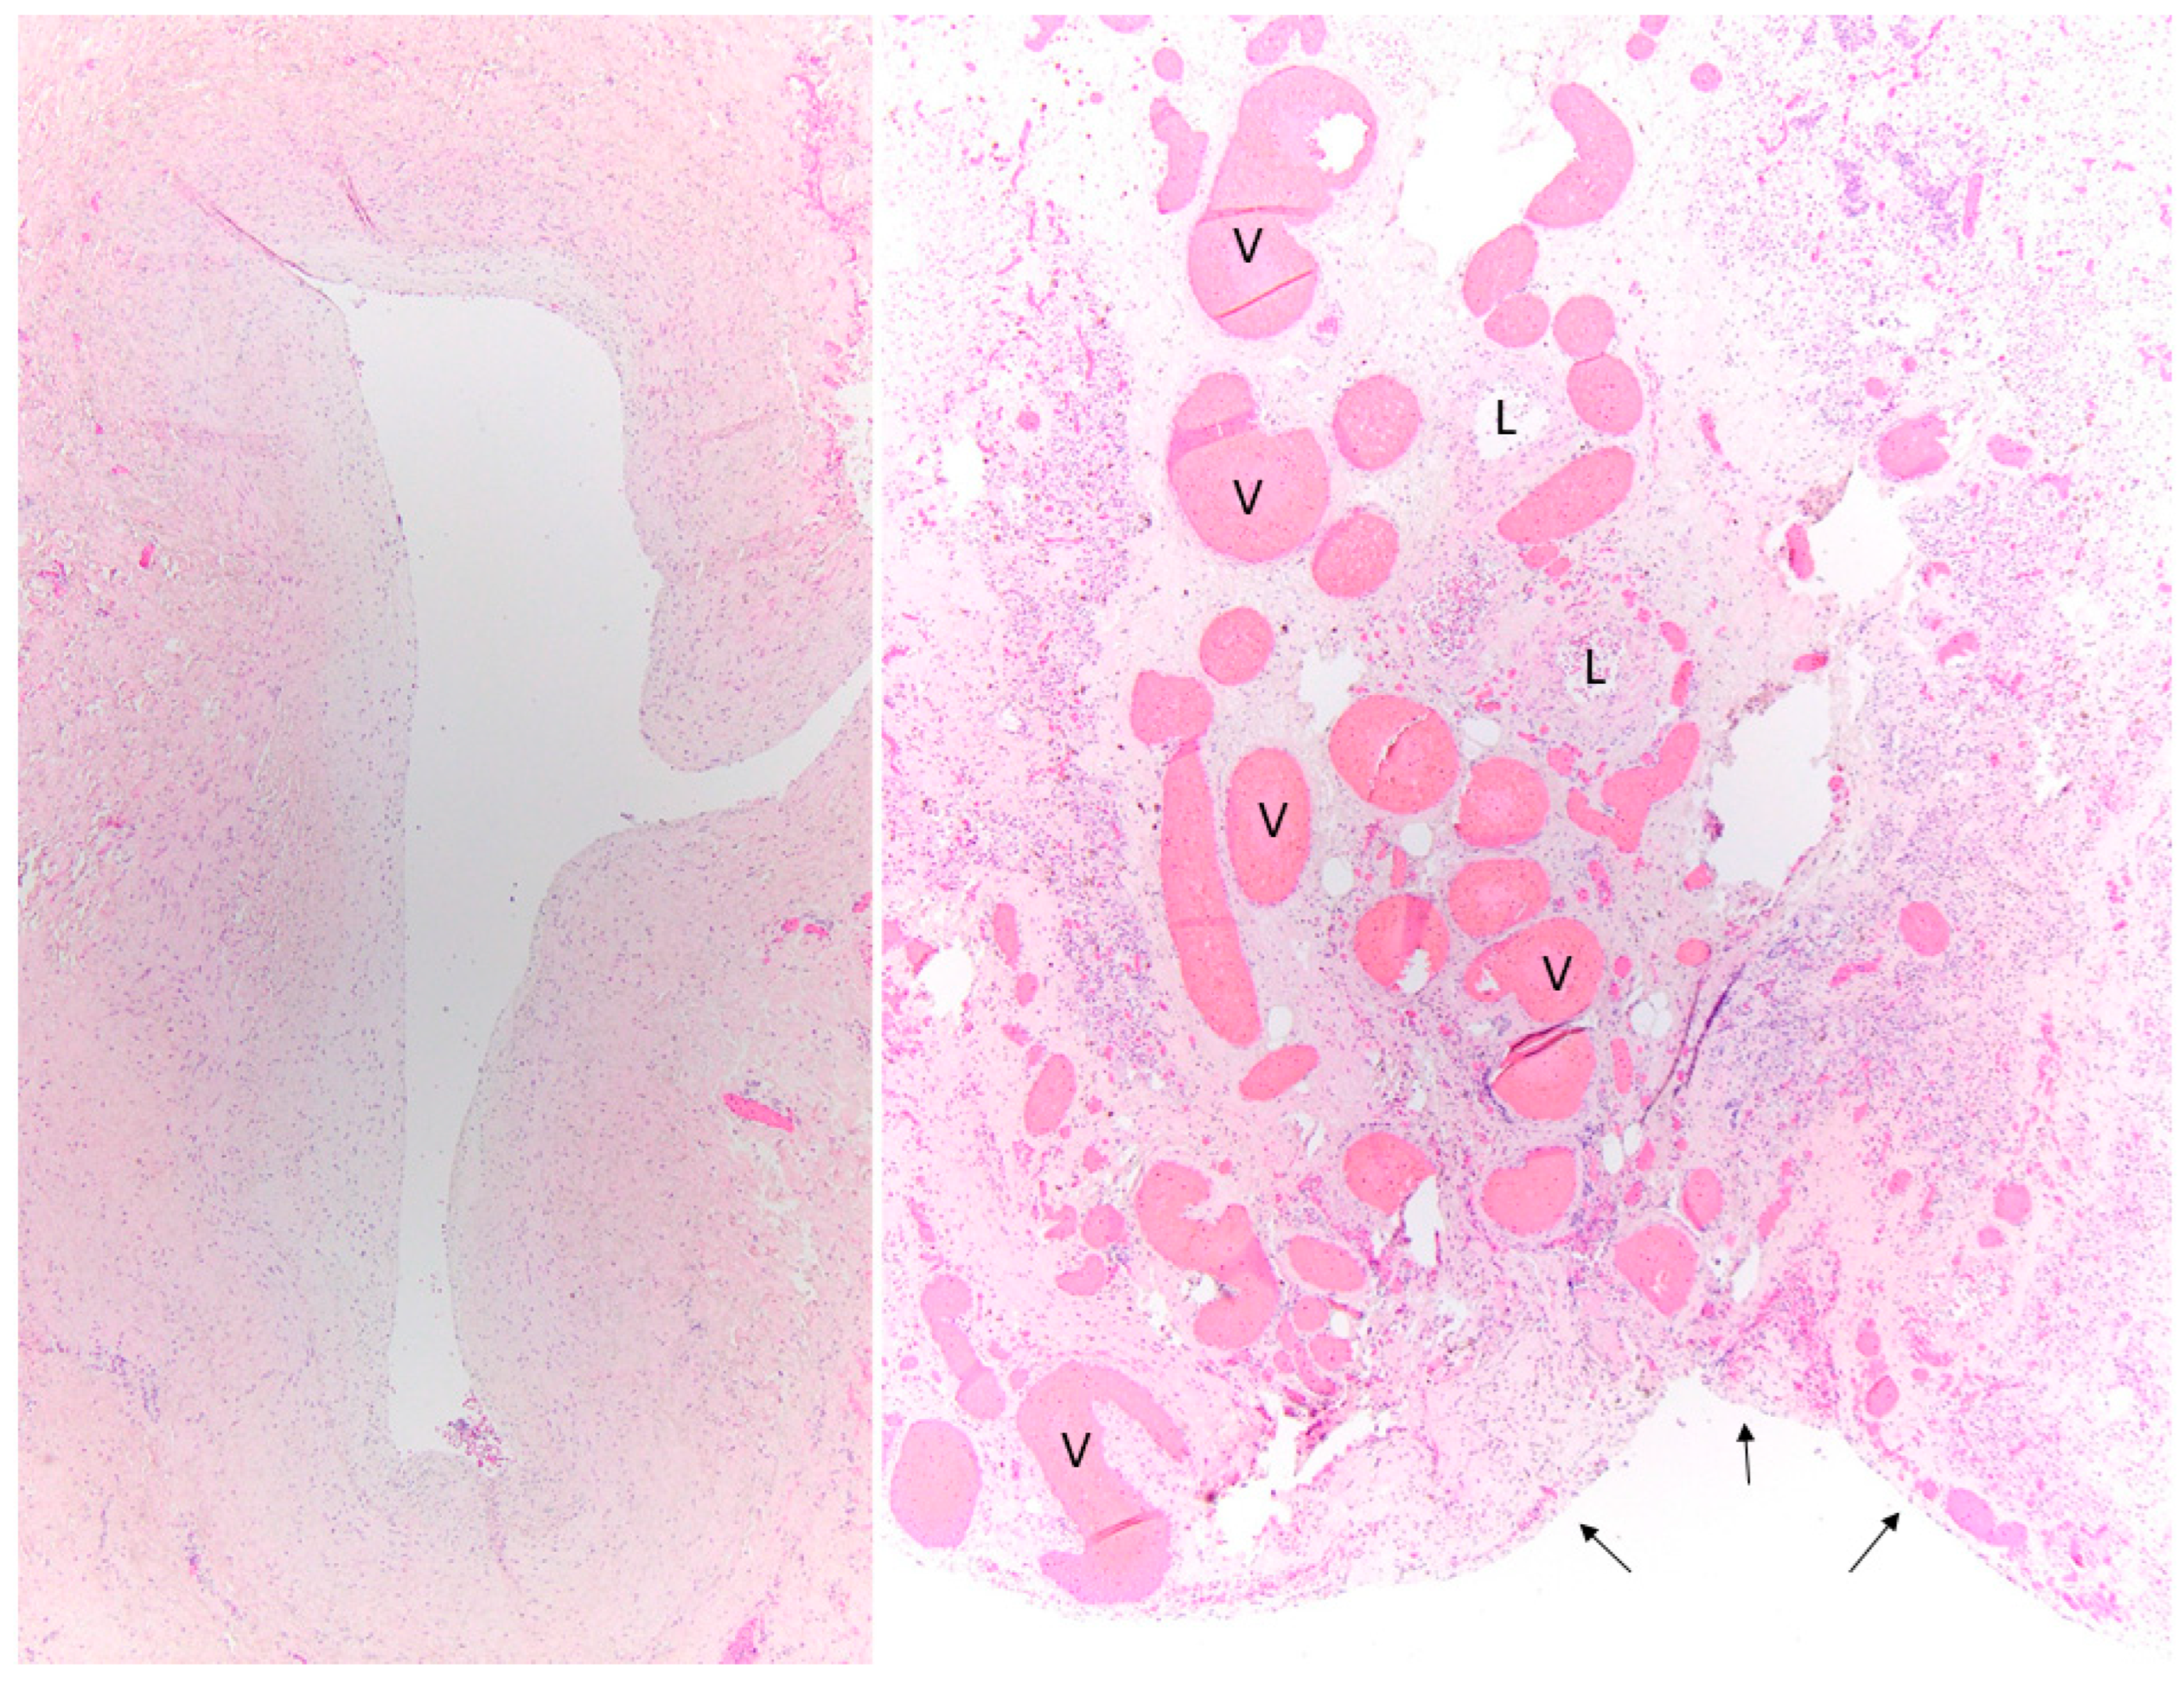

- Kovach, A.E.; Magcalas, P.M.; Ireland, C.; McEnany, K.; Oliveira, A.M.; Kieran, M.W.; Baird, C.W.; Jenkins, K.; Vargas, S.O. Paucicellular fibrointimal proliferation characterizes pediatric pulmonary vein stenosis: Clinicopathologic analysis of 213 samples from 97 patients. Am. J. Surg. Pathol. 2017, 41, 1198–1204. [Google Scholar] [CrossRef]

- Pogoriler, J.E.; Kulik, T.J.; Casey, A.M.; Baird, C.W.; Mullen, M.P.; Jenkins, K.J.; Vargas, S.O. Lung Pathology in Pediatric Pulmonary Vein Stenosis. Pediatr. Dev. Pathol. 2016, 19, 219–229. [Google Scholar] [CrossRef]